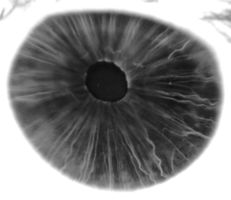

في البشر ومعظم الثدييات والطيور، القزحية ( Iris ؛ الجمع: قزحيات أو قزحية العين) عبارة عن هيكل حلقي رقيقة في العين ، المسؤولة عن السيطرة على قطر وحجم الحدقة وبالتالي كمية الضوء الوصول إلى شبكية العين . يتم تحديد لون العين من خلال القزحية. من الناحية البصرية ، البؤبؤ هو فتحة العين ، بينما القزحية هي الحجاب الحاجز .

القزحية تتكون من طبقتين: الطبقة الصبغية الليفية الوعائية الامامية المعروفة باسم سدى ، وتحت سدى خلايا الظهارية المصطبغة.

ترتبط السدى بالعضلة العاصرة ( العضلة العاصرة الحدقة )، والتي تنقبض الحدقة بحركة دائرية ، ومجموعة من العضلات الموسعة ( الحدقات الموسعة ) التي تسحب القزحية بشكل شعاعي لتكبير الحدقة وتسحبها في ثنايا.

كإثبات عملي، طبع الباحثون ختماً بنمط يشبه العضلات المجهرية في قزحية العين البشرية. تتكون القزحية من حلقةٍ عضليةٍ تُحيط بالحدقة. تتكون هذه الحلقة العضلية من دائرةٍ داخليةٍ من أليافٍ عضليةٍ مُرتبةٍ مركزياً، مُتبعةً نمطاً دائرياً، ودائرةٍ خارجيةٍ من أليافٍ تمتد شعاعياً، كأشعة الشمس. يعمل هذا البناء المُعقد معاً على تضييق أو توسيع الحدقة. بمجرد أن ضغطت رامان وزملاؤها نمط القزحية على حصيرة هيدروجيل، غطوا الحصيرة بخلايا معدلة وراثياً للاستجابة للضوء. في غضون يوم واحد، سقطت الخلايا في الأخاديد المجهرية وبدأت بالاندماج مع الألياف، متتبعةً أنماط القزحية، لتنمو في النهاية لتُشكّل عضلة كاملة، ببنية وحجم مماثلين للقزحية الحقيقية. عندما حفّز الفريق القزحية الاصطناعية بنبضات ضوئية، انقبضت العضلة في اتجاهات متعددة، على غرار قزحية العين البشرية. وتشير رامان إلى أن القزحية الاصطناعية التي صممها الفريق مصنوعة من خلايا العضلات الهيكلية، المسؤولة عن الحركة الإرادية، بينما تتكون الأنسجة العضلية في قزحية العين البشرية الحقيقية من خلايا العضلات الملساء، وهي نوع من الأنسجة العضلية اللاإرادية. وقد اختاروا تصميم خلايا العضلات الهيكلية بنمط يشبه القزحية لإظهار القدرة على تصنيع أنسجة عضلية معقدة ومتعددة الاتجاهات.